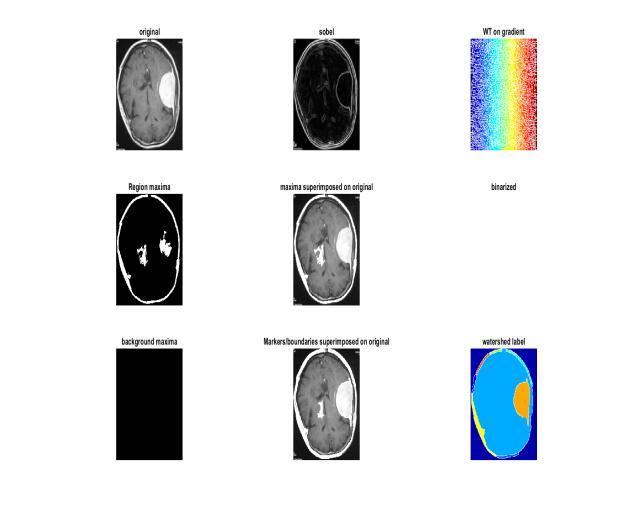

process is shown in Figure 1 from start to finish. Because the morphological formation is a structural form, as a reference for erosion, we construct a disc shaped structure. The picture is converted to grey, then opened morphologically after a variable separation. If the difference is less than the threshold, the limit function convertsasegmentedimagewithameaningfulchangetoa pixelvalueof0,and255ifthedifferenceislarge.Thenext step istheduplication reduction processthatoccurs after thisgraytransitiontoa complete binary image.When the image is reconstructed using an image mask, the foregroundandbackgroundobjectsappeartobedifferent. The black streaks and stem marks disappear when the bottles are opened one by one. To find the relevant previous tags, the distribution is now calculated by re sizingtheimageandcomputingtheregionalmaxima.After that, we overlay this pre image marker and clean the border and marking blocks, as well as any missing pixels, using repeated closures and erosions. We must first computetheEuclideanrangetransformofagrayorbinary picture. We needto splitit into watersheds. Furthermore, theSobelfunctiongavebetterresultsforedgerecognition anddiscriminationthantheCannyvariant,thusSobelwas selected.

Before identifying tumors, we must now perform morphological enhancements on the first segmented imageproducedbypre processingtheimages.Addingand removing pixels, as well as contrast changes known as dilationanderosion,arethemostbasicsteps.Byreplacing the markers in the foreground image, we use several rounds of masking and marking to identify. The whole

Tumor identification is a strategy that has gained a considerable lot of interest in the last several years, and the most optimal method is to use a marker controlled conventional watershed transformation. Denoising techniqueshaveevolvedovertimeandcanbeemployedin combination with conventional filters, offline filters, and nonlinear anisotropic separation. They are used in the Markov field approach [16], the wavelet based approach [17], and the analytical correction process. Water separation is a 92.76 percent better classified technique that gets its name from the natural process of collecting waterinreservoirsandtheintroductionofgrayimagesas geographicsites. When submergedin water,local minima are thought to resemble holes in which they raise the water level and bring it closer to the surface. Water is collected in vessels equal to the water flow of the earth's surfacebytheflowatthebottomofitsslopes.Adamisthe widest point or intersection of two bodies of water, and these dams or water lines divide the picture into several groups. This is a water separation procedure where the MRI is completed and the gray image images are filled with linear lines that distinguish between different dimensions as a boundary. Dehydration is a popular method because it can also dissociate noncancerous body tissues.

back, which are part of the dark area that should be separated.Boundariesatboththefrontandbackmarkers are necessary to create water flow, so the transition process can begin now. In order to enlarge the tumor furtherandproduceacleardistinctionbetweentumorand brain,weperformwatershedsegmentationasecondtime. We can now view the tumor as the original black and whiteimagebecausethethresholdwas255forthetumor and 0 for the rest. We were able to identify the markers anddefinetheboundariesaccuratelybyreconstructionby repeated opening and closing, ensuring that there was no disaggregation. Superimposition was employed [19] to enhance contrast and ensure that borders were not highlightedwithclear tumorsvisibleagainstapitch black background.

The border method and regional approach are the two major techniques of segmentation. Watershed segmentation combines these two methods to provide a robust tool to quickly locate edges and areas. Watershed transformation is a segmentation method based on morphologicalgradient[20].

Fig:1Depictsthewholeprocess Fig:2Depictstheinfection